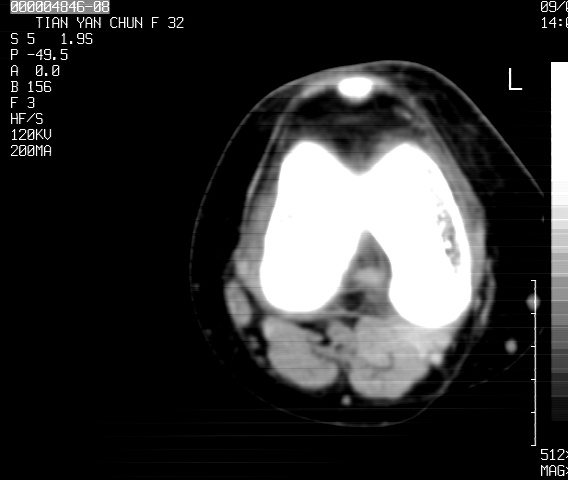

标题: CT18487:请会诊,女32岁,左膝疼痛数日 [打印本页]

标题: CT18487:请会诊,女32岁,左膝疼痛数日

关节面软骨有硬化环考虑退行性变

定位片可见髁间棘骨质增生,支持膝关节退行性变。

定位片可见髁间棘骨质增生,支持膝关节退行性变。建议mri 检查

考虑骨性关节炎